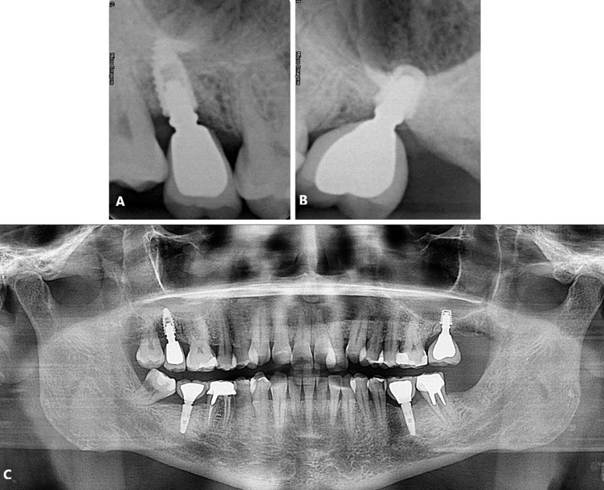

Foram solicitados exames complementares, incluindo radiografia panorâmica e tomografia computadorizada, para avaliação precisa da região anatômica, permitindo a quantificação da espessura e altura óssea (Figura 01. A-D). O plano de tratamento consistiu pela instalação de implantes ultrashort ARCSYS (FGM, Joinvile – SC, Brasil) 4,3 mm x 5,0 mm.

Figura 01. A – D) Exames de imagem complementares evidenciado aspecto inicial da região atrófica na maxila superior direita (área do elemento dental 16).

Figura 02. A, B) Etapa operatória da instalação do implante dental curto. C, D) Tratamento finalizado. Aspecto final com a reabilitação protética-implante.

Figura 03. A, B) Radiografias periapicais final.